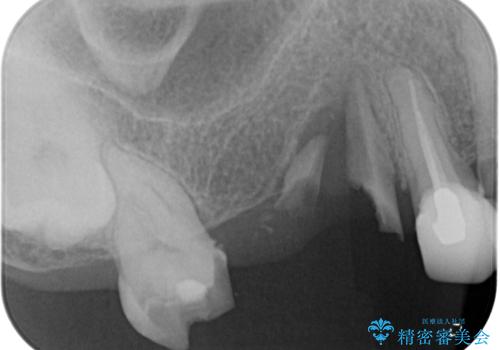

- 欠損や破折により失われた奥歯に、インプラント治療を希望して来院された患者様です。

欠損部はすぐにインプラント埋入が可能で、手前の歯根が残存している部位も、できれば抜歯をして奥と一緒に埋入をしたいところでしたが、破折による炎症が大きいため、2回に分けてインプラント埋入を行うこととしました。